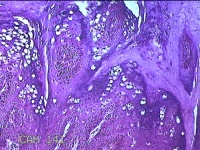

右侧拇指皮下结节

性别

男

年龄

40岁

临床诊断

皮下结节

一般病史

发现右侧拇指皮下结节1年余,无明显疼痛及不适。

标本名称

大体所见

灰白暗红色带皮肤结节0.8x0.3x0.2cm一个,表面糜烂,切开结节呈实性,切面灰白粉红色,质中。

图1